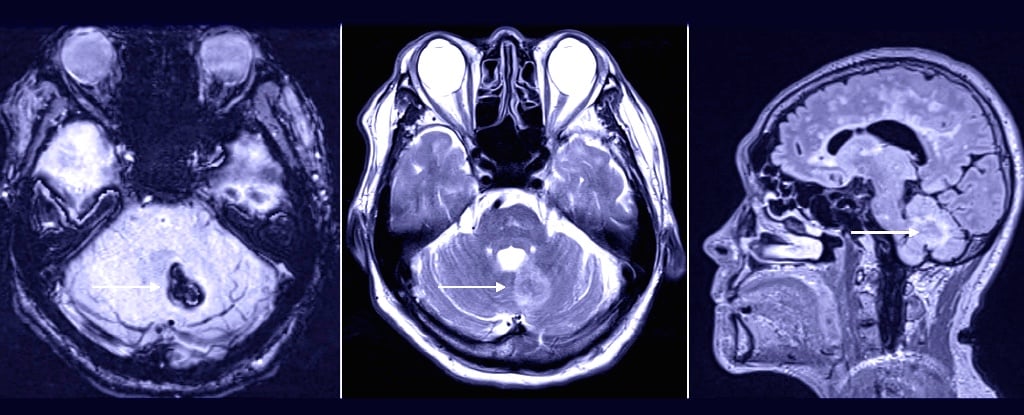

Dr. Tim Williams, a 69-year-old Florida physician who previously directed Delray Medical Center's Proton Therapy Institute, survived a fall that caused a brain bleed and a nine-day coma, underwent a bedside craniotomy, and endured a lengthy recovery before returning home. Nine months on, he’s about 80% back to normal, has shifted toward radiation oncology research, and credits Delray Medical Center’s staff and stroke expertise with saving his life. He emphasizes that anyone experiencing stroke symptoms should seek care at a stroke center to maximize chances of survival.